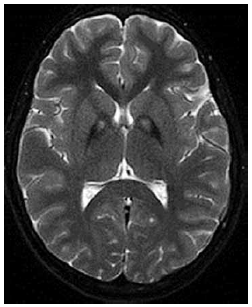

Menino de 10 anos de idade apresenta história progressiva de distonia, disartria e regressão cognitiva. A ressonância magnética de crânio revela o seguinte achado na imagem.

Qual o gene mais provavelmente associado ao quadro?